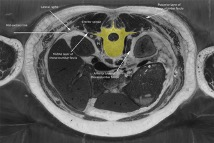

To emphasize the different volumes, cross-sections are shown below of (Figure 1) the vertebral column in yellow, and (Figure 2) the larger vertebral column region in amber color.